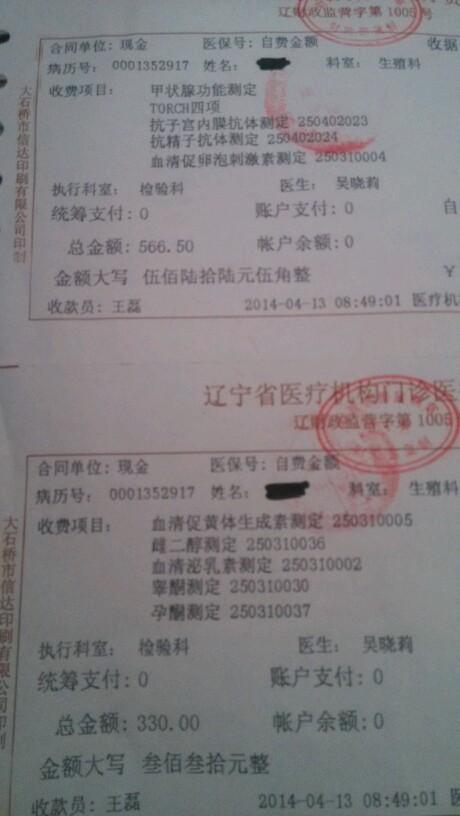

做输卵管造影要多少钱?专家解读造影费用

超生输卵管造影费用图片合集